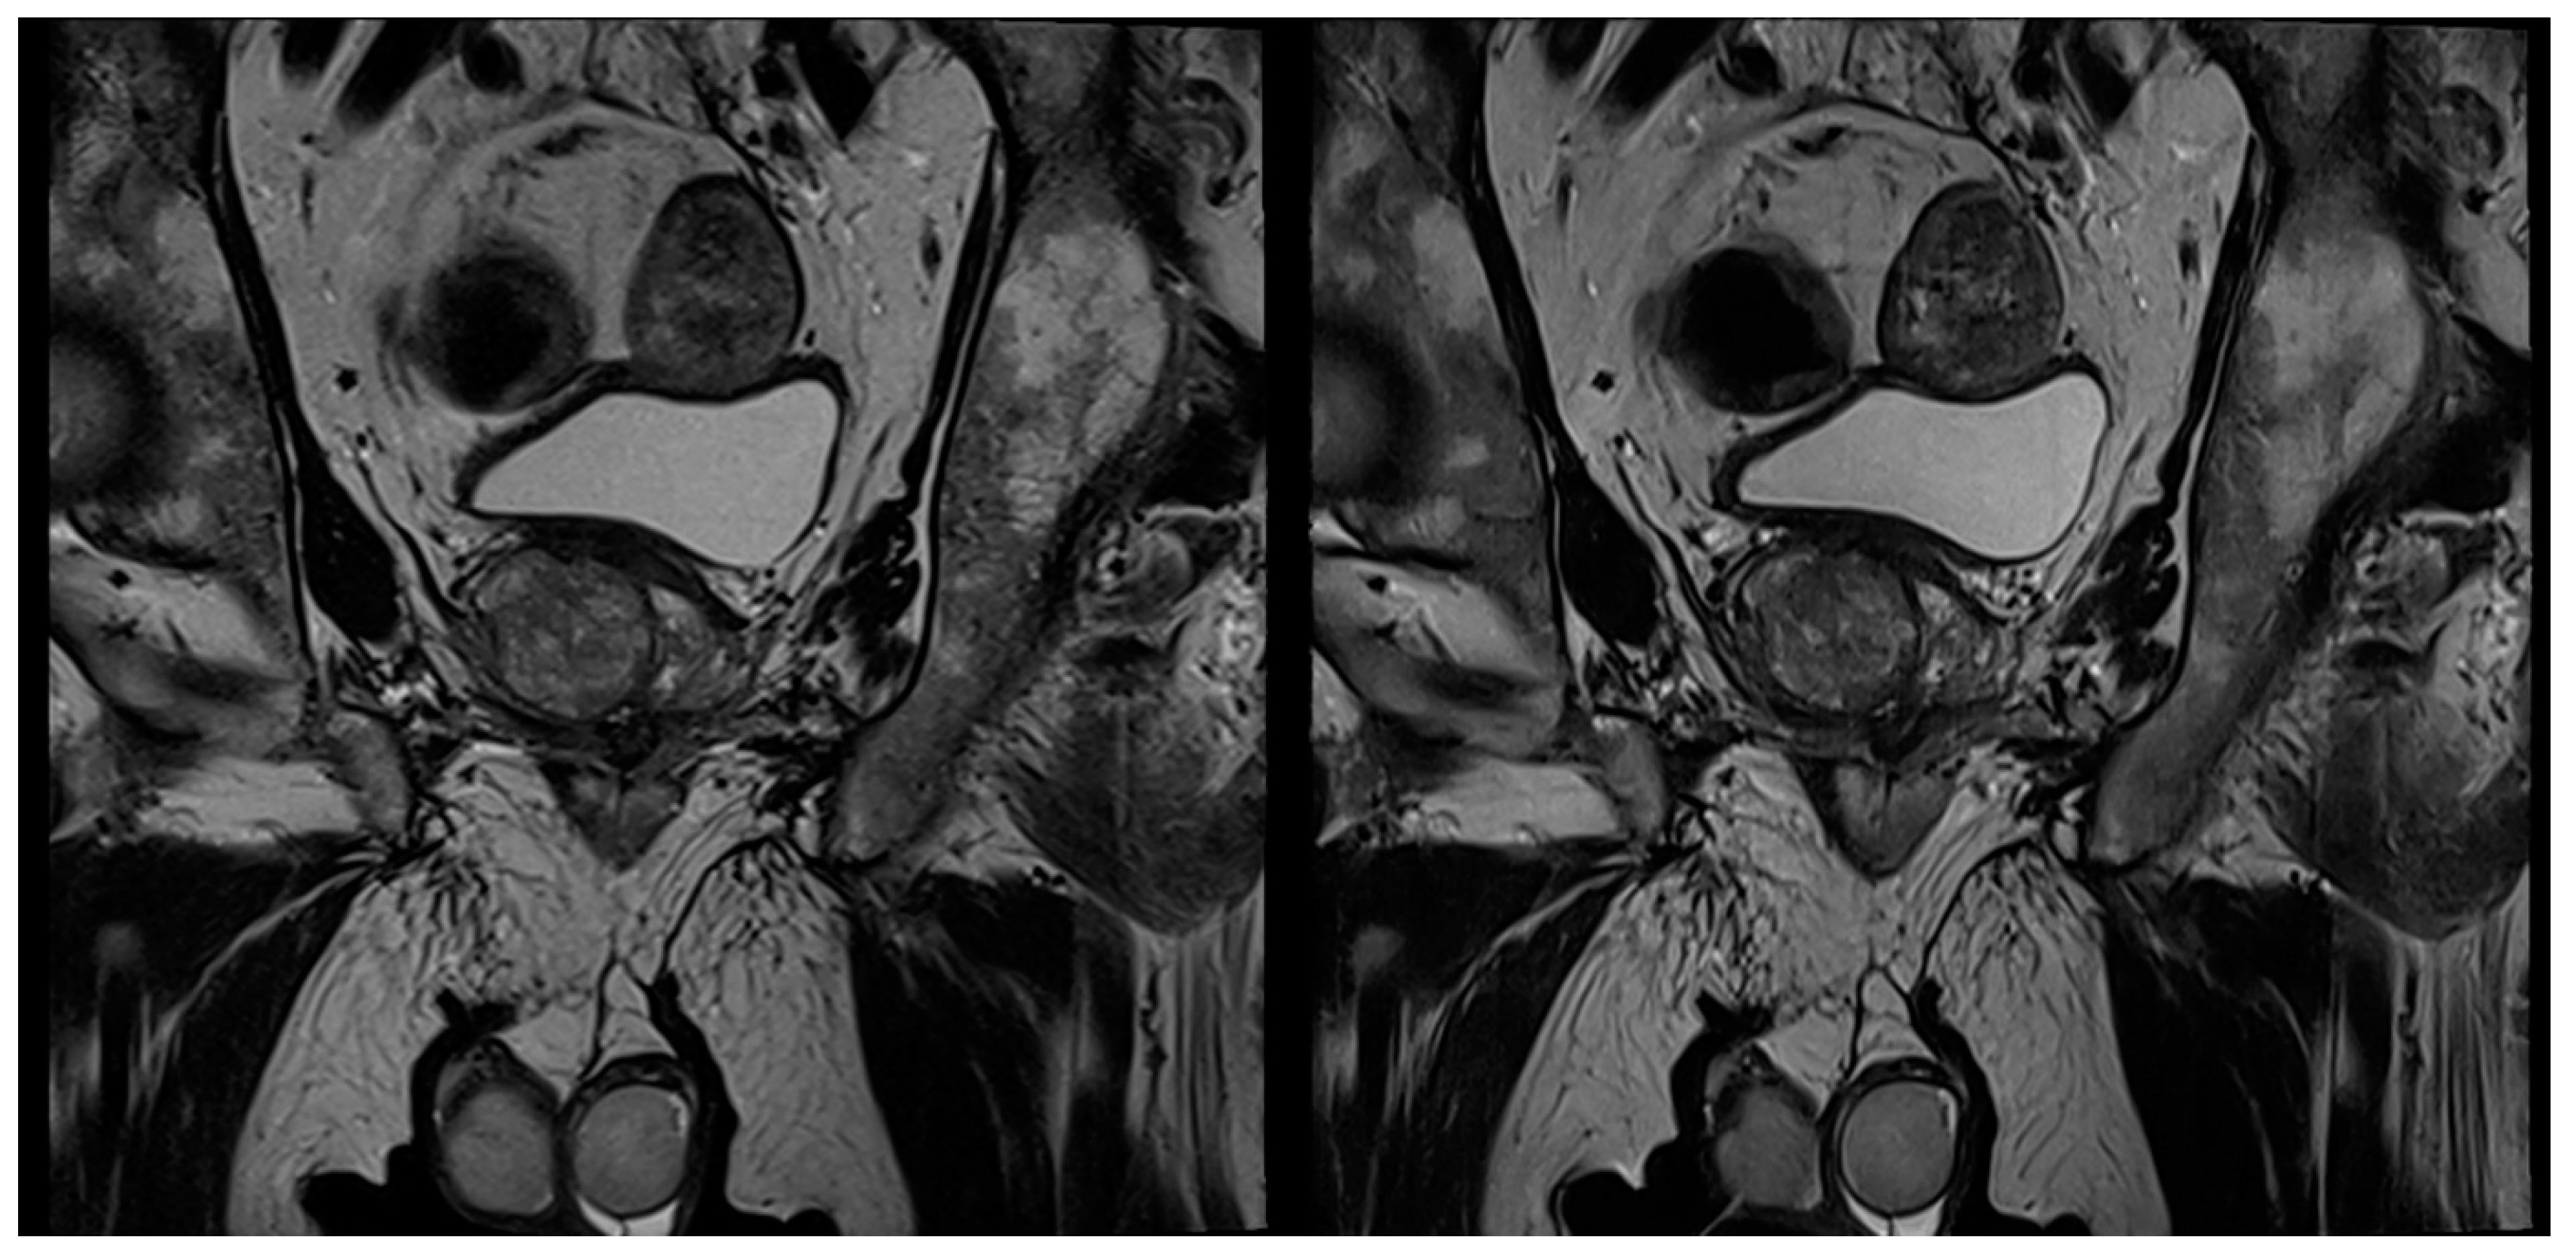

3.2. Evaluation of Qualitative Imaging Parameters

3.3. PI-RADS Scoring and Lesion Conspicuity

| Image noise coronal | 3 (3–3) | 4 (4–4) | <0.001 | 3 (3–4) | 4 (4–4) | <0.001 |

| Image noise sagittal | 3 (3–3) | 4 (3–4) | <0.001 | 4 (3–4) | 4 (3–4) | 0.005 |

| Overall image quality coronal | 3 (3–4) | 4 (4–4) | 0.002 | 3 (3–4) | 4 (4–4) | <0.001 |

| Overall image quality sagittal | 3 (3–4) | 4 (3–4) | 0.002 | 3 (3–4) | 4 (3–4) | 0.005 |